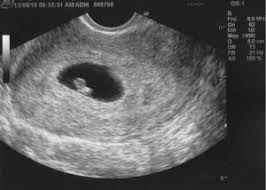

كيس حمل داخل الرحم في الاسبوع السادس شهر ونصف يحتوي على كيس المح ولا يحتوي على جنين Youtube

كيس الحمل الفارغ في الاسبوع السادس زيادة

تجربتي مع كيس الحمل الفارغ